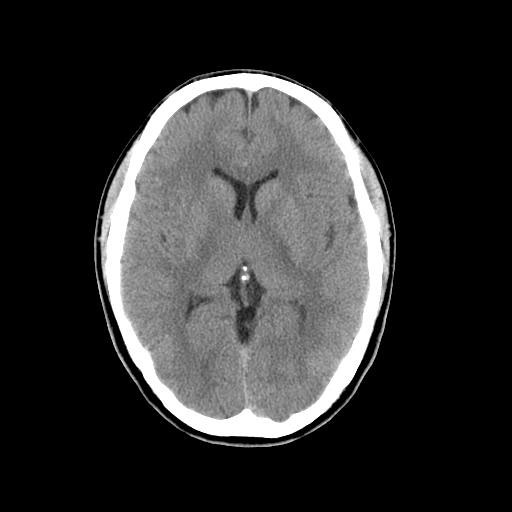

CT検査は様々な方向からX線を当て体内の水分や骨、空気など成分の違いを区別して画像を生成することで、レントゲン等では得ることができない臓器の状態を詳細に把握することが可能となり、小さい腫瘍などをより明確に映し出すことができます。

また、多角的に体内の断面図を得ることができるため立体的に構造を理解することが可能になり、病変の位置や広がりをより詳細に判断することが可能になります。

CT装置は列数が多くなると一度に広範囲の撮影が可能となり、息止め時間が短くなるため少ない負担で検査を受けて頂けます。また、より細かい断層(輪切り)画像を撮る事ができ、病変の抽出能が上がることは早期発見に繋がります。